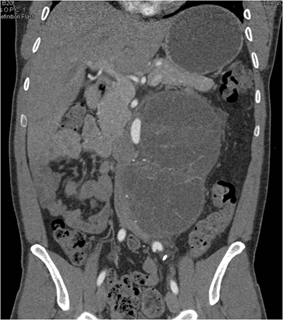

In this 42 year old male the best diagnosis is?

lymphoma pre-treatment

lymphoma post treatment

liposarcoma

germ cell tumor